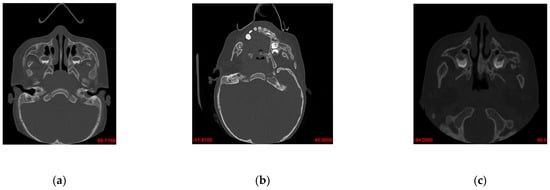

3.2. After the First Surgical Procedure and First Physiotherapy (Age—25 Months)

- shorter mandibular body (gn–go) in spite of an increase in its length by 1.85 mm on the left side and by 3.37 mm on the right side (Table 1),

- smaller breadth of the lower mandible (bigonial breadth, go–go) in spite of an abrupt increase in the dimension by 4.56 mm in comparison with that in the examination prior to the surgical procedure (Table 1),

- increased height of the body in the area of the mandible symphysis (gn–id; height at the site of mental foramen), which was confirmed in direct measurements (Table 1) and relative measurements in relation to the body length (value of index i4; Table 3); this is an effect of the process of backward rotation;

- upheld larger angle of the mandible (go–gn–go; Table 2);

- correct breadth of the superior mandible (kdl–kdl; kdm–kdm; intercondylar distance, internal and external; Table 1),

- symmetrical length of the entire mandible (gn–kdl); a decrease in the degree of asymmetry by 4.93 degrees,

- asymmetrical length of the body toa light degree (Table 5),

- asymmetry of the angle of the mandible (gonial angle), which underwent transformation from moderate to severe asymmetry (increase by 5.33 degrees; Table 5).

3.3. After Second Surgical Procedure and Second Physiotherapy (Age—54 Months)

- shorter body (gn–go) and shorter rami of the mandible (go–kdl) in spite of an increase in dimensions in relation to those from the previous examination (Table 1),

- smaller breadth (bigonial breadth, go–go) in spite of an increase in dimensions in relation to those from the previous examination (Table 1),

- further increase in the body height in the area of the mandible symphysis (gn–id)—an effect of progressing backward rotation (Table 1),

- upheld considerably larger angle of the mandible (go–gn–go; Table 2);

- correct breadth of the superior mandible (kdl–kdl; kdm–kdm; intercondylar distance, internal and external),

- preserved symmetry of the length of both the entire mandible and the body (Table 5),

- moderate asymmetry of the body height at level M2 (Table 5);

- light asymmetry of the height of both rami (go–kdl), the right ramus was shorter than the left one (the operated one); an increase in growth on the operated side (Table 5),

- severe asymmetry of the gonial angles (alpha). The right-hand angle was larger than the left-hand angle by 11.88 degrees (Table 5).